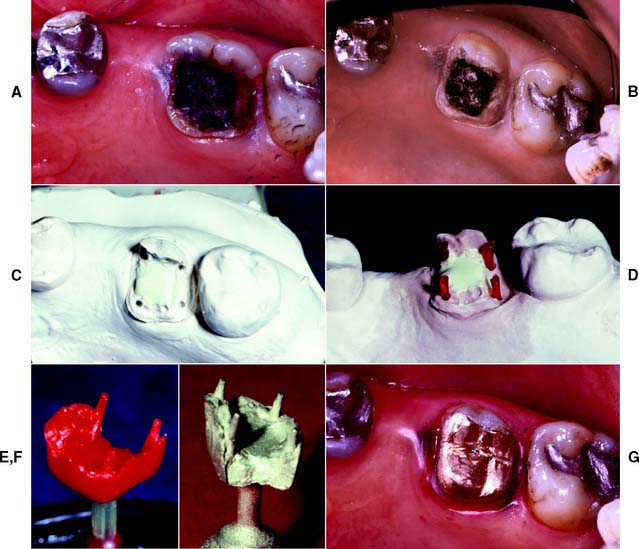

A free (detached) autogenous gingival graft (Fig. 6-13) is used to increase the width of attached gingiva in areas where it is deemed inadequate. The donor site most commonly used is the hard palate, although any area of keratinized tissues, such as an edentulous ridge or the retromolar pad, may be suitable.

Fig. 6-13 Free autogenous gingival graft. A, Planned abutment tooth lacking adequate keratinized gingiva. B, The recipient site is prepared. C, The graft is sutured to place. Some apical adjustment is needed around the premolar before application of the surgical dressing. D, The healed graft. (Compare the width of attached keratinized gingiva here with that in part A.) The defective restoration can be treated at this stage.

The recipient bed site is prepared by making a horizontal split-thickness incision just coronal to the mucogingival junction. As the incision passes apical to the junction, it may become either split thickness or full thickness.36,37 The recipient bed is trimmed of tissue tags and thinned. (A template of tinfoil may be used as a guide for the correct size and shape of the graft.) The graft is then carefully removed from the donor site, and any fat or glandular tissue is excised, so that a maximum thickness of 1 mm is left. Sterile saline is used to keep the graft moist until it is placed on the recipient bed for a check of size and shape, and it is then further shaped if necessary. When the proper dimensions have been attained, the graft is sutured into place. Finally, the graft site and the donor site may be covered with a surgical dressing. Complete healing requires approximately 6 weeks,38,39 at which time the donor site and the grafted site should appear normal.